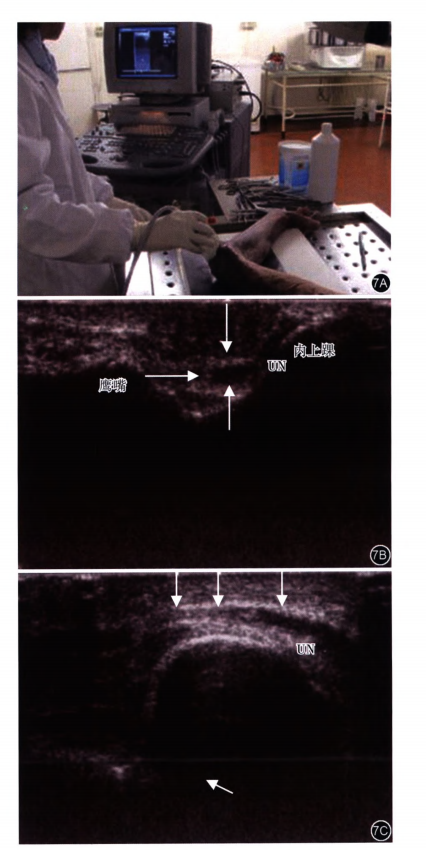

图 7

肘部尺神经超声检查及影像表现

9

注:UN为尺神经;7A上肢检查体位为患肢取外展屈肘90º,后外旋平放于检查床上;7B超声探头横向置于肱骨内上髁和鹰嘴之间,箭头所指为尺神经横断面;7C尺神经长轴超声影像,在神经上方清晰可见一薄层高回声纤维组织影.为Osborne's韧带